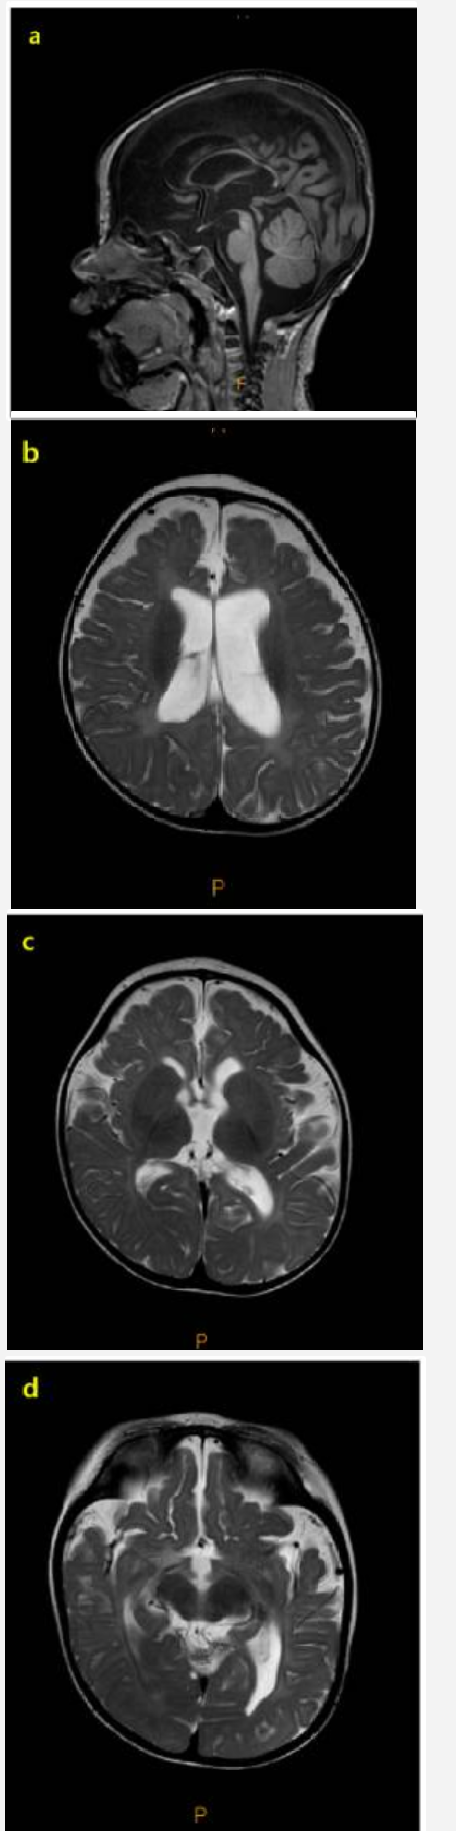

对患者进行了初步评估,以确定癫痫发作的病因和里程碑式的发育迟缓。脑MRI显示弥漫性脑萎缩,以脑脊液腔外扩大、脑沟明显、胼胝体变薄为特征(图1)。癫痫发作期间捕获了发作期脑电图(EEG),其特征是弥漫性棘波、多棘波和多波放电,随后是电衰减期。发作间期脑电图显示多灶性棘波放电,伴有高振幅背景活动,诊断为高度节律失常和婴儿癫痫痉挛综合征(图2)。患者接受氨己烯酸治疗,起始剂量为50 mg/kg/天,逐渐增加至150 mg/kg/天。然而,由于持续性癫痫痉挛,开始使用大剂量类固醇进一步治疗。经胸超声心动图和腹部超声检查未见异常。

婴儿癫痫痉挛综合征基因检测MRI

图1:患者脑部磁共振成像 (MRI) 表现。患者脑部 MRI 表现。T1 加权矢状面图像 (a) 可见变形的薄胼胝体。弥漫性脑萎缩也很明显,其特征包括明显的轴外间隙、体积减小的脑沟明显以及白质髓鞘形成延迟 (b-d)。